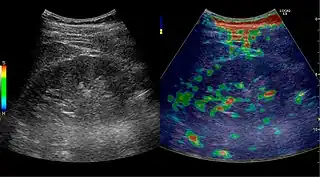

CEUS, image fusion and elastography

Contrast-enhanced ultrasound (CEUS) can evaluate microvasculature, which color Doppler US is unable to detect. In renal US examination, CEUS can be used to differentiate tumor and pseudotumor, such as prominent columns of Bertin. Pseudotumors enhance as adjacent renal tissue. The use of CEUS is recommended in special cases to distinguish between cystic and hypovascularized solid lesions, to characterize complex cysts, abscesses, traumatic lesions and ischemic lesions.[1]

Solid malignant tumors in the kidney do not exhibit specific enhancement patterns like some liver lesions, and no valid enhancement criteria between benign and malignant renal lesions have been proposed. However, CEUS is used in some patients after ablation of renal cell carcinoma to evaluate contrast uptake in the treated area (Figure 30).